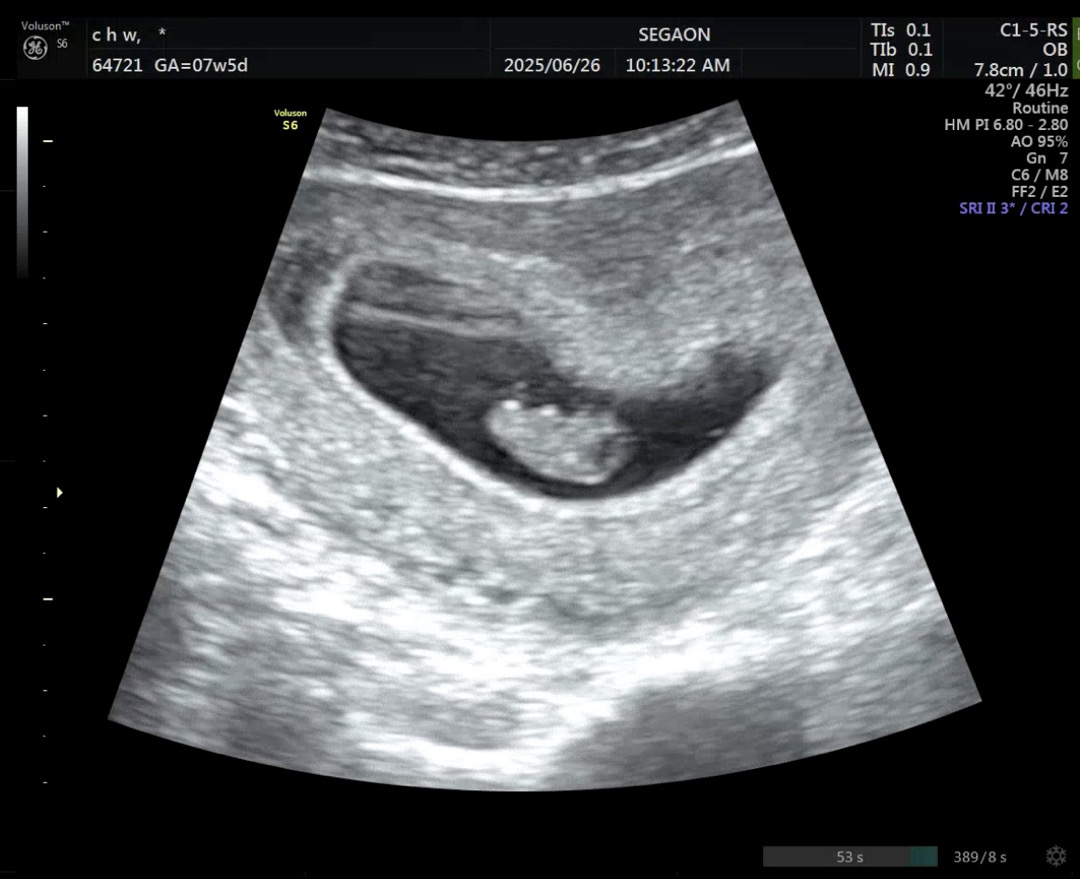

지난주에 정기검진 다녀오고 잘있나 궁금해서 어제 다른 병원에서 보고 왔어요 >_< 1.5cm로 지난주보다 2배 넘게 커진거 있죠 ㅋㅋ 아직 입덧이 없어서 맛난거 많이 먹어서 쑥쑥 크나봐요 ! 딸내미일지 아들내미일지 너무 궁금해요.... 16주 언제 와ㅠㅠㅠㅠㅠ

저 오늘로 7주6일이요! ㅎㅎ 코딱지만한게 넘 귀여워요,,,ㅠㅠ